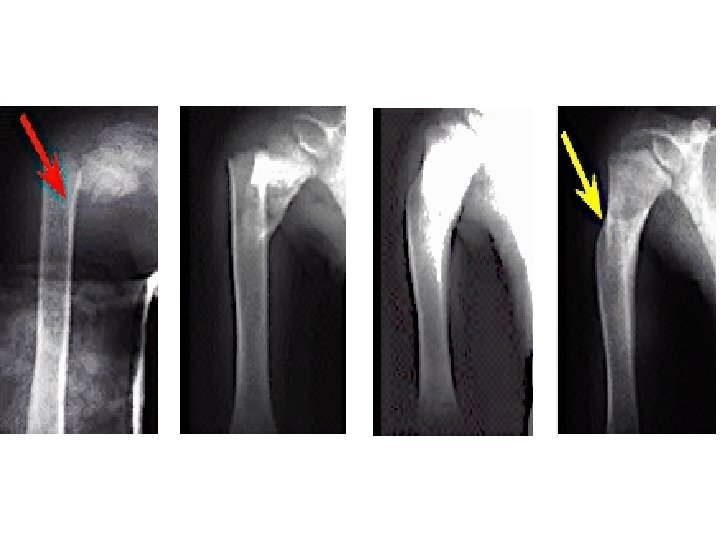

Femoral Shaft Fractures

Femoral Shaft # • 1. 6% of all pediatric # • M>F • Age: – (2 – 4) years old – Mid-adolescence • Adolescence >90% due to RTA

Femoral Shaft #- Mechanism of Injury • Direct trauma: – RTA, – Fall, or • Indirect trauma: – Rotational injury • Pathologic #: – Osteogenesis imperfecta – Nonossifying fibroma – Bone cysts – Tumors

Femoral Shaft #- Treatment 6 – 12 y: • Flexible I. M. N • Bridge Plating • External Fixation

Femoral Shaft #- Treatment 6 – 12 y: • Flexible IMN • Bridge Plating • External Fixation

Femoral Shaft #- Treatment 6 – 12 y: • Flexible IMN • Bridge Plating • External Fixation: – Multiple injuries – Open fracture – Comminuted # – Unstable patient

Femoral Shaft #- Treatment 12 y to skeletal maturity: • Intramedullary fixation with either: – Flexible nails, or – Locked I. M nail

Femoral Shaft #- Treatment Operative Indications: • • • Multiple trauma, including head injury Open fracture Vascular injury Pathologic fracture Uncooperative patient

Femoral Shaft #- Complications • Malunion – Remodeling will not correct rotational deformities • Leg length discrepancy – Secondary to shortening or overgrowth • Muscle weakness • Nonunion (rare)